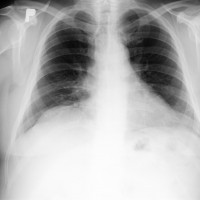

Choroby dotykają każdego z nas. W dzisiejszych czasach jesteśmy narażeni na różnego rodzaju wirusy, dolegliwości i tym podobne. Dlaczego miałbyś ryzykować? Czy nie lepiej mieć święty spokój i dbać o siebie bardziej niż kiedykolwiek? Poniżej przedstawione są popularne i najczęściej spotykane choroby i dolegliwości. Zapoznaj się z nimi najlepiej teraz, póki nie jest na to za późno. Zapraszamy do lektury.